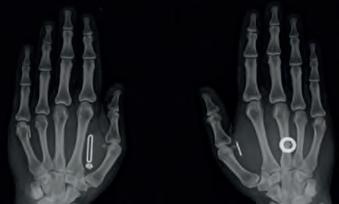

Consenting to being microchipped by your employer sounds farfetched, but allow me to introduce you to the United States of America. In 2017, a US company got headline writers around the world jostling for clicks after implanting radio-frequency lll

identification (RFID) microchips into the hands of 50 willing employees.

“Once you put technology inside the body, it is covered under the same scope and privacy laws that are contained within GDPR in the EU and HIPAA here in the United States. So I have protections at a governmental level that are, essentially, hackers tools.” Noe tells me this not as someone smug to be pulling the wool over the FBI’s eyes, but with genuine concern at the potential for this to be used by bad actors. Noe, who now has 11 devices inside him, from magnets in his fingers to the key to his crypto wallet, admits he will wear Faraday gloves if he’s likely to be around other hackers, so as to prevent them from compromising his own chips, many of which he’s advertised the exact location of.

Opposite page: Len Noe’s implanted hands Clockwise from right: Adam Scott’s character Mark Scout in Severance; Lem Noe, a cybercriminal turned implant enthusiast; The first wave of implanted chips were used to pay at vending machines; Biohax founder and CEO Jowan Österlund